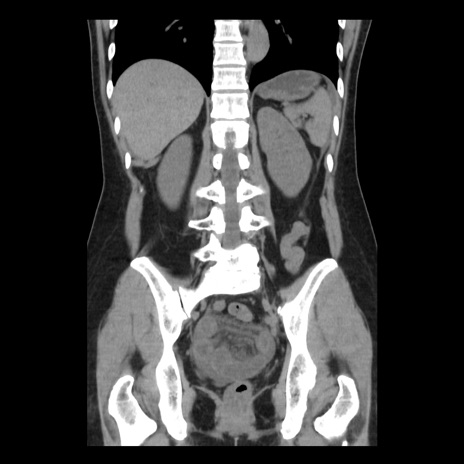

症例10(冠状断像)

【症例】 50歳代女性

【主訴】 腹痛

【現病歴】前日生レバーを食べた。今朝に排便あり。 昼前に突然発症の腹痛を生じ、当院救急外来を受診した。

【既往歴】 子宮筋腫にてで子宮全摘後

【身体所見】 意識清明、腹部:平坦、軟、下腹部やや左を中心に圧痛・反跳痛あり、筋性防御あり

【データ】WBC 7800、CRP 0.07